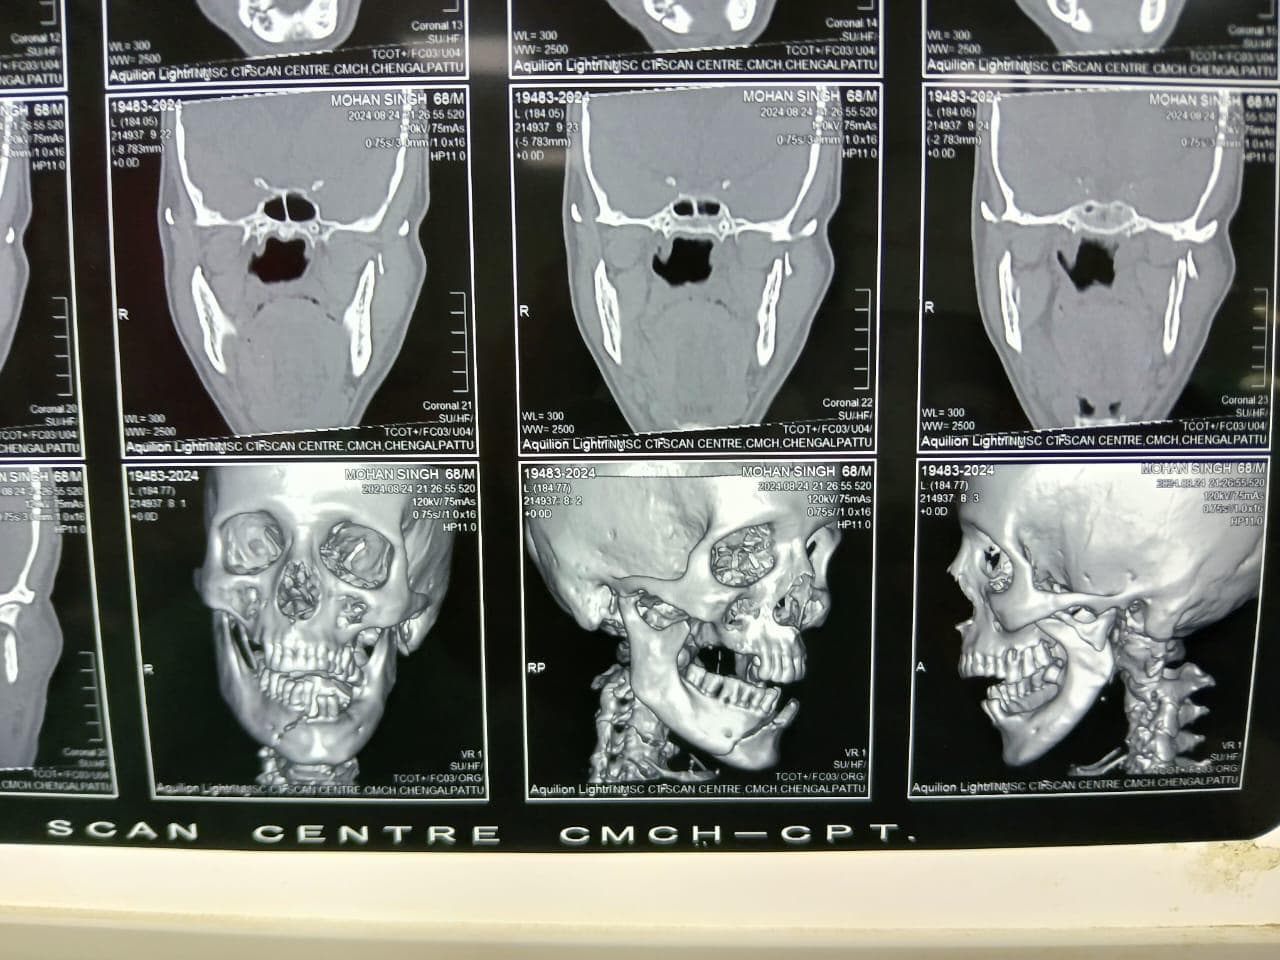

Mandibular Fracture Fixation focuses on restoring anatomical bone alignment, maintaining a proper dental occlusion (bite), and stabilizing the jaw for functional recovery. Before treatment, patients face severe pain, difficulty speaking or swallowing, and potential permanent facial deformity or malocclusion. After surgery, patients benefit from stable internal fixation, restored jaw function, and the ability to return to a normal diet and oral hygiene routine.